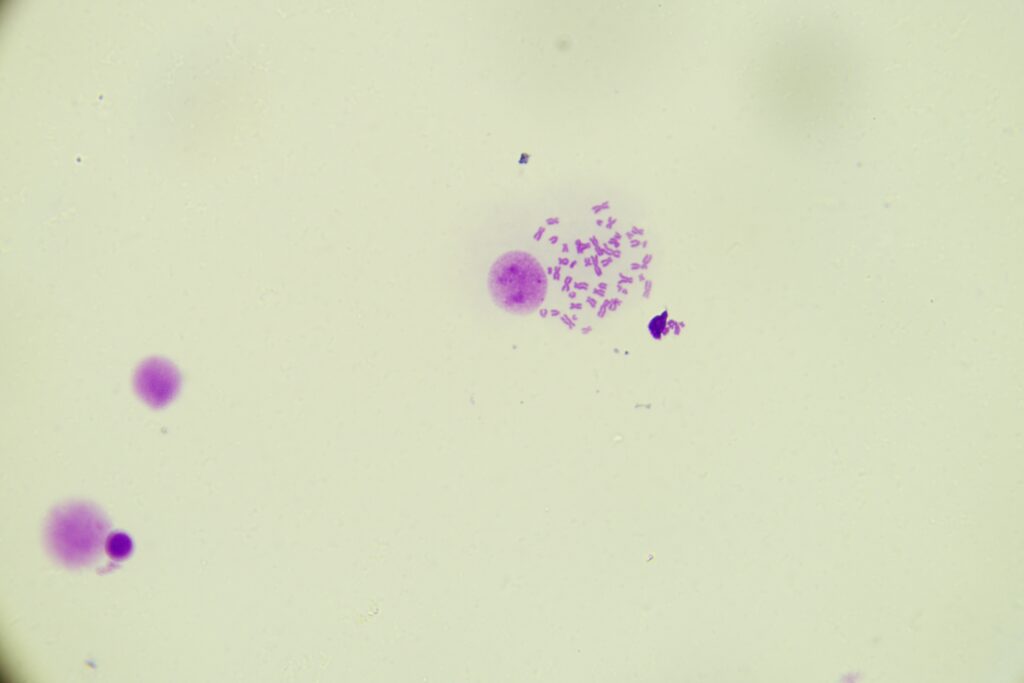

Chromosomy ludzkie XX

Chromosomy ludzkie XX